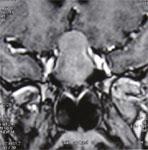

МРТ мозга должно проводиться с контрастной визуализацией. При обнаружении опухолевого образования в области гипофиза следует проконсультироваться с нейрохирургом.

Рис. 1. МРТ мозга с контрастом. Эндосупраинфраселлярная макроаденома гипофиза, сжимающая зрительные нервы и III желудочек мозга.